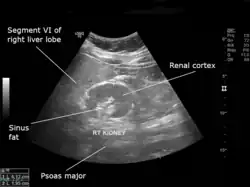

An ultrasound scan of a hypoplastic right kidney in an adult male. | |